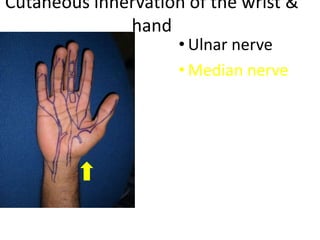

- Naming the bones, joints, tendons, nerves and skin landmarks of the hand and wrist.